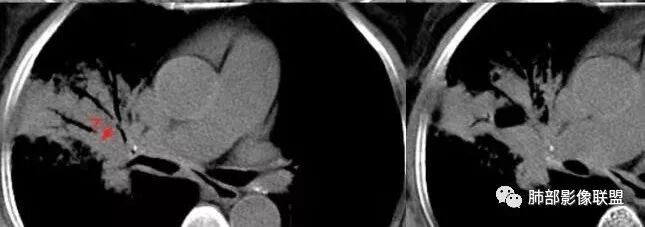

胸CT:右肺上叶实变内可见支气管充气征,近端支气管狭窄,远端扩张,周围可见毛玻璃影,右肺中叶支气管闭塞,并可见气道壁钙化,右肺中叶体积缩小,实变内可见空洞,并可见气液平面,空洞周围可见毛玻璃样影,右肺下叶支气管开口狭窄,右肺门淋巴结肿大。纵隔窗可见病灶与壁层胸膜间隙增宽,考虑良性病变-----感染性病变------TB?

右肺上叶病变,内见钙化及空洞,支气管可见,考虑结核伴出血。

主动脉弓旁有个增大淋巴结,稍圆鼓,但似乎有点钙化,右上肺病变外周也有少许钙化,肺炎性肺癌可以外周有钙化的

这里是中叶的不张和空洞,有钙化,结核确实也不能排除

实变区像支气管爬行征?空洞区也有钙化和边界清楚模玻璃影

3.熊老师告诉我们:肺结核可以有磨玻璃,这个我以前一直不知道,右肺门淋巴结有钙化,病灶内纵膈窗隐约细细点状钙化,所以结核磨玻璃可以,